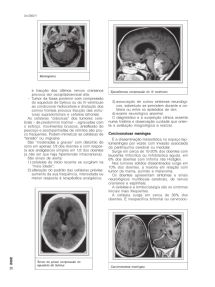

Meningioma

e tracção dos últimos nervos cranianos Ependimoma compressão do IV ventrículo

provoca dor occipital/cervical alta.

–Tumor da fossa posterior com compressão

do aqueduto de Sylvius ou do IV ventrículo 3) associação de outros sintomas neurológi-

ao condicionar hidrocefalia e dilatação dos cos, sobretudo se persistem durante a ce-

cornos frontais provoca tracção das estru- faleia ou entre os episódios de dor;

turas supratentoriais e cefaleia bifrontal. 4) exame neurológico anormal.

DOR Tumor da pineal compressão do

20 aqueduto de Sylvius Carcinomatose meníngea